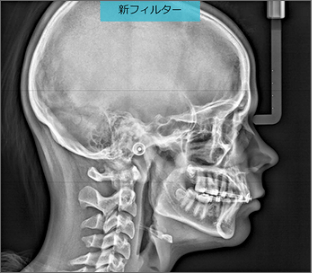

スキンラインの認識も骨の視認性も向上した新セファロ画像

- 新CS Adaptフィルターにより、スキンラインが認識しやすくなります。

- 画像強調をアップさせ、計測ポイントとなる骨の視認性も改善しています。

同一患者の治療中、別日程で撮影した画像